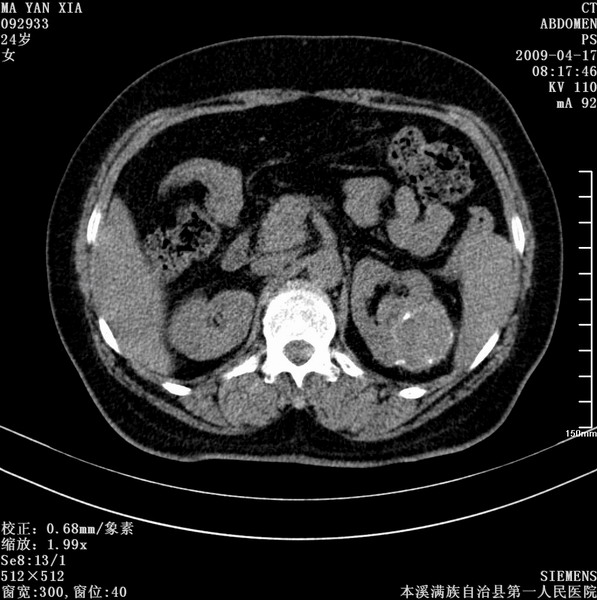

标题: CT19443:肾脏肿瘤两个区强化不一样。 [打印本页]

标题: CT19443:肾脏肿瘤两个区强化不一样。

女,51岁,体检时发现肾脏占位,建议ct增强。无任何自觉症状。

典型的不均匀强化,左肾癌

肾盂癌或肾癌侵犯肾盂

肾盂癌或肾癌侵犯肾盂。